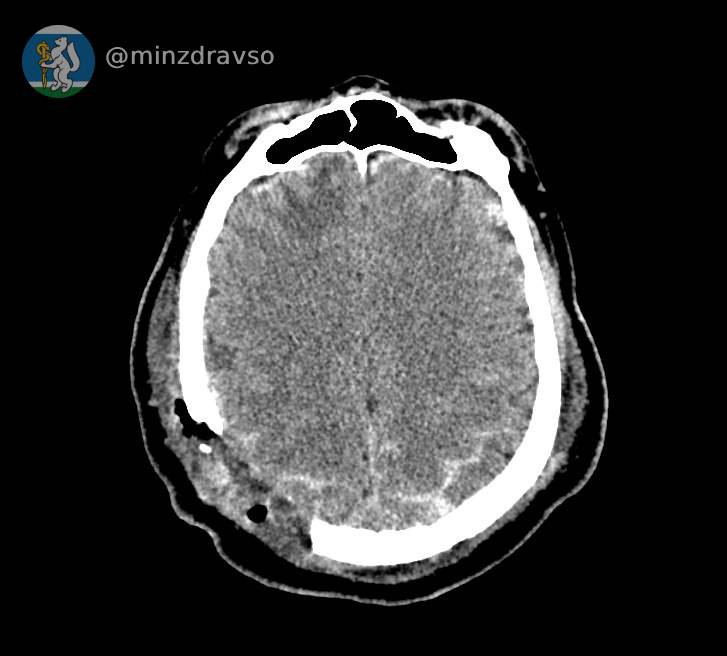

В Серове 57-летнего мужчину ударила стрела строительного крана, расколов ему череп. В критическом состоянии мужчина поступил в единственное на севере нашего региона стационарное отделение скорой медицинской помощи, действующее на базе Серовской городской больницы. Высокоточный компьютерный томограф помог быстро диагностировать травмы и выявить расположение повредивших мозг костных отломков, самый острый из которых мог в любую минуту стать причиной гибели пациента. Слаженное взаимодействие серовских реаниматологов позволило стабилизировать состояние пострадавшего.

Профильные специалисты из Екатеринбурга в ходе телеконсультации подтвердили необходимость перегоспитализации уральца в ближайший межмуниципальный медицинский центр. Мужчину экстренно доставили в Городскую больницу №1 Нижнего Тагила, где его ожидала операционная бригада. Нейрохирург Дмитрий Неволин, анестезиолог-реаниматолог Аслам Абдуев и операционная медсестра Нина Дмитриева удалили отломки костей, гематомы, восстановили целостность твёрдой мозговой оболочки.